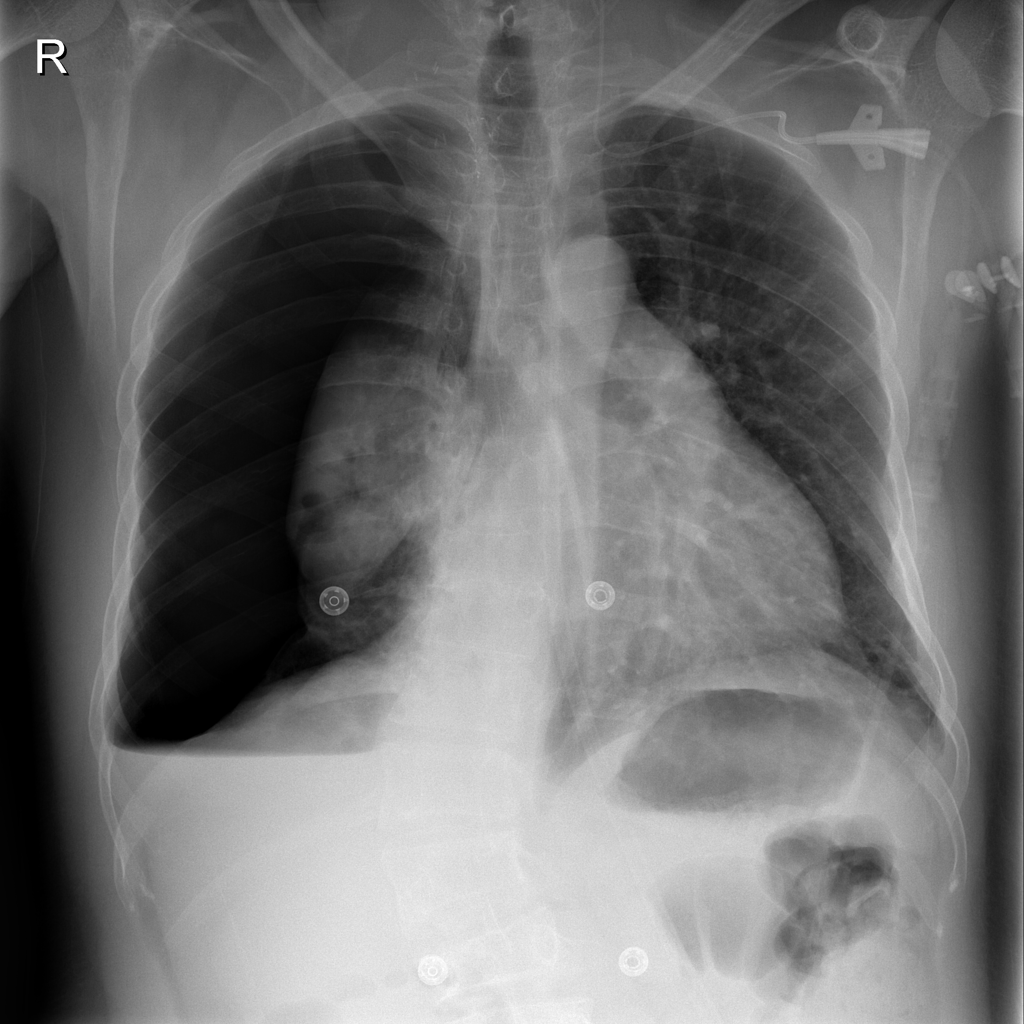

PAT-B9C3 · IMG-003Atelectasis

PAT-B9C3 · IMG-003

PA